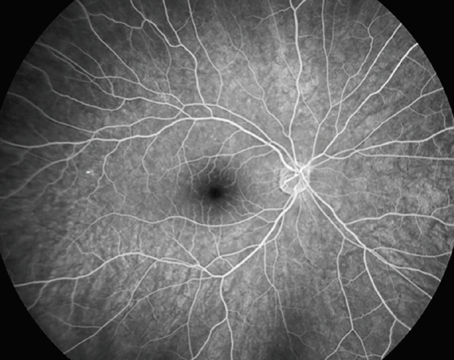

Retinal microvascular metrics: The emerging role of swept-source OCT angiography